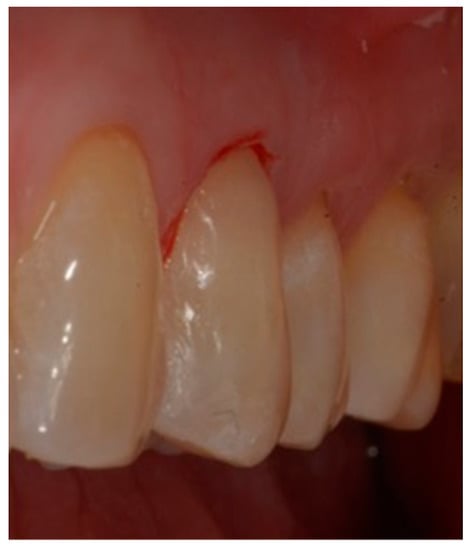

- Selection of the shades (dentinal masses and enamel) of the tooth to be restored (Figure 1);

- Initial measurement of the length of the clinical dental crown (performed with a millimeter periodontal probe placed adjacent to the dental crown and having as a reference the most apical part of the gingival sulcus and the highest part of the crown) and photography of the lesions at time 0 (t0) (Figure 2a).